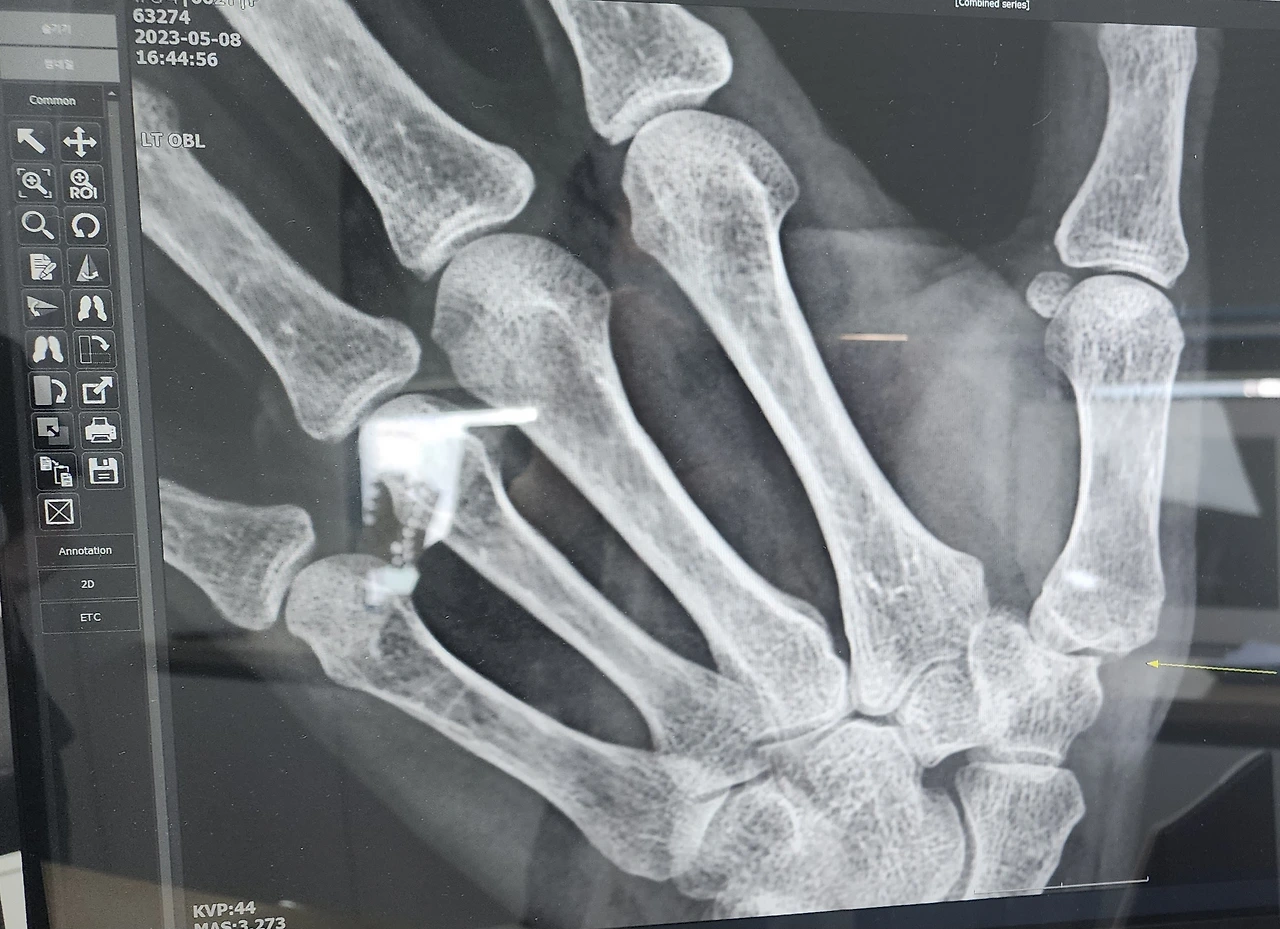

손 엑스레이를 보았다. 다른 손가락 네 개는 뼈가 정상으로 잘 붙어 있는데 엄지손가락은 뼈가 살짝 어긋나 있었다. 관절염이라고 했다. 선생님 말씀으로는 다치지 않았다면 더 오래전부터 아팠을 거라고 하셨다. 조금씩 아팠는데 내가 둔해서 알아차리지 못한 것 같다. 병원에 처음 왔으니 삼일 정도 물리치료를 받아보고 그다음에 다시 보자고 하셨다. 조퇴하고 사흘 동안 파라핀 치료와 레이저 치료를 받고 약도 먹었다. 4일째 되는 날 의사 선생님께 진료받았다. 사흘 동안 치료를 받고 어떠냐고 물어보셨다.

동생에게 엑스레이 사진을 보냈더니

"뼈가 문제가 아니라 손을 많이 써서 생기는 관절염이야. 심하면 방아쇠 뭉치 손이 되어서 손가락이 퉁겨지는 것 같이 될 수 있어. 약 먹고 좀 쉬게 하면 괜찮을 거야."